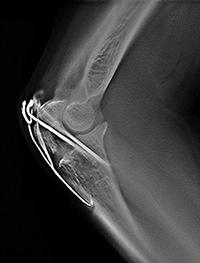

金属のアーチファクトが低減でき,

骨折など金属固定している部分の

経過観察に有用

3.金属アーチファクトの低減

整形外科領域にて,ボルトやプレートなど金属固定された部位の術後の経過観察を行う場合に,画像診断を困難にしている金属アーチファクトが抑えられるため,骨の癒合状態などの金属周囲の骨評価が容易である。